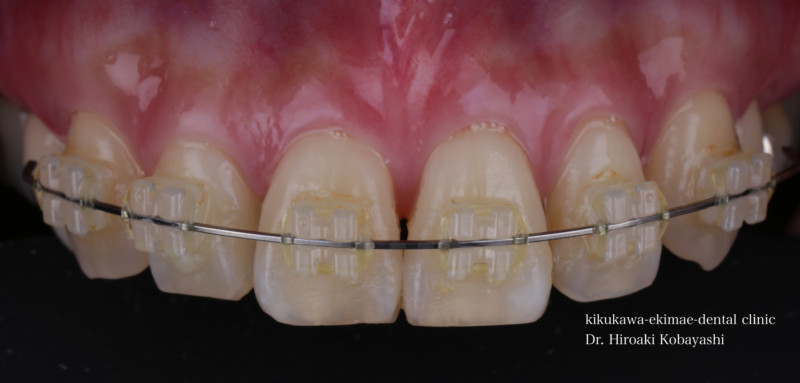

歯並びを気にされて来院されました。見た目改善を目的にワイヤーによる部分矯正を希望されました。 ブラケット装着用のマウスピースを作り、ブラケット装着を行います。   弱い力をかけながら、ワイヤーにより歯を動かします。強い力を急にかけると歯の根が吸収されてしまいます。なので弱い力で歯を動かすことによって根への負担が少なく歯根吸収のリスクが少なくなります。               6ヶ月程度で歯の並びを改善することができました。   before after